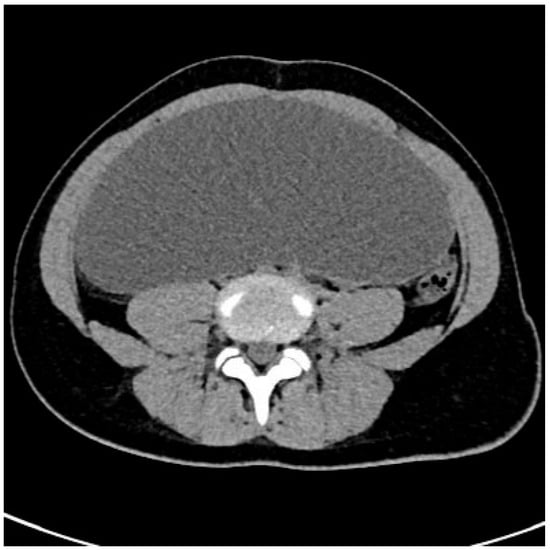

2. Detailed Case Descriptions